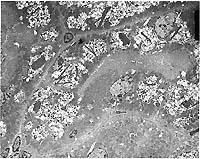

- Transmission Electron Micrograph, 1540X. Kidney, proximal

tubules. The electron micrograph illustrates portions of four

proximal tubules lined by tall cuboidal epithelial cells with

a brush border, oval nuclei with dispersed chromatin and 1-2

small nucleoli, and abundant mitochondria, many arrayed perpendicularly

to the basement membrane. The epithelial cells are swollen, vacuolated,

and have numerous, intracytoplasmic osmiophilic amorphous deposits

(secondary lysosomal contents) surrounded by an electron-lucent

space and a single membrane (fused lysosomes) and large, rectangular,

rhomboid or irregular to needle-like crystalline intralysosomal

deposits (alpha 2m globulin). Interspersed between the proximal

tubules (lower left) are small spindle cells with oval nuclei

(mesangial cells).

- Case 12-4. Electron micrographs

- Many of the tubular epithelial cells in the central tubule

at the center of the photo are swollen and expanded more laterally

than apically due to the vacuolated inclusions. Residual cellular

organelles are peripheralized and compartmentalized. The compartmentalized

mitochondria have lost proper orientation and are no longer aligned

perpendicular to the basement membrane. In the epithelial cell

in the center of the photo, the lateral cell boundaries are markedly

widened, and the nucleus is compressed and flattened against

the cell base (see cell labeled "4" at AFIP website).

- Extensive intracytoplasmic vacuolation is present in the

tubular epithelium. Determining the nature of these vacuoles

is difficult due to the low magnification of the electron micrograph,

but there is evidence that the vacuoles represent enlarged and

giant lysosomes. First, of the various organelles that can become

dilated in renal tubular epithelial cells, only the lysosome

regularly contains material of varying size, shape, and density.

The material within many of these vacuolated structures appears

to be multiple lysosomes within one unit membrane. In one or

two vacuoles, the individual lysosomal membranes disappear, forming

one large vacuole (see center bottom tubular epithelial cell

in photo, or refer to AFIP website with cell labeled "1").

Second, several vacuoles contain homogenous, medium electron-dense

material suggestive of lysosomal contents (see cell labeled "2"

on AFIP website). Normally, lysosomal contents are very electron-dense

when tissue is fixed in 1% glutaraldehyde; however, the contributor

does not mention method of tissue fixation in this case, and

the preservation of lysosomal material may have been altered

by an alternative fixative.

The globular to rhomboidal, electron-dense, intracytoplasmic

bodies present in the tubular epithelial cells are consistent

with the alpha 2m globulin hyaline inclusions seen in rat hyaline

droplet nephropathy. However, the intracytoplasmic acicular (needle-like)

crystals observed in this case are not characteristic of rat

hyaline nephropathy, but rather are more consistent with the

microcrystals observed in cyclodextrin-induced nephrosis in the

male rat. The renal toxicity of cyclodextrins is manifested ultrastructurally

as increased vacuoles within the apical cytoplasm of the proximal

tubular epithelial cells, with the eventual formation of giant

lysosomes, and the presence of acicular microcrystals within

the lysosomal matrix. Cyclodextrins are known to form complexes

with several cellular compounds, including lipids, cholesterol,

and lipoproteins. The acicular crystals may represent cyclodextrin

complexed to alpha 2m globulin in renal tubular epithelium.